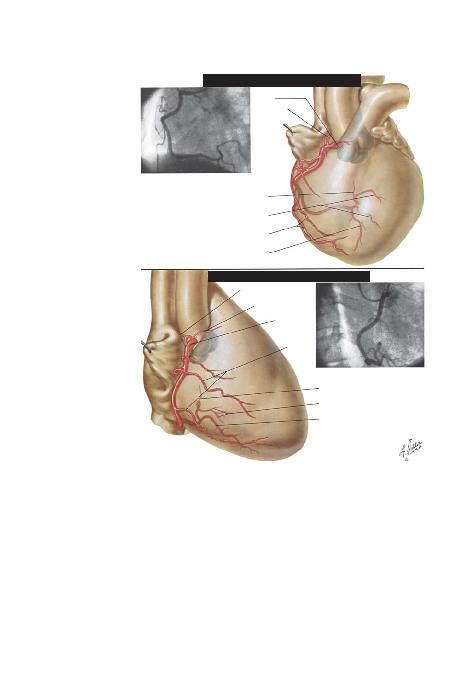

BÖLÜM I -- LEVHA 30

SA/ KORONER ARTER: SOL ANTER

SA/ KORONER ARTER: SA/ ANTER

SA/ ANA KORONER

ARTER

S-A NODUNA

G

A-V NODUNA G

S-A NODUNA G

KONUS DALI

SA/ ANA

KORONER

MARJDALLAR

SOL VENTRDALLAR

POSTER(DESENDAN) DAL

MARJ

POSTER

SOL VENTR